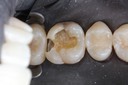

Alan Chinn #28 prep